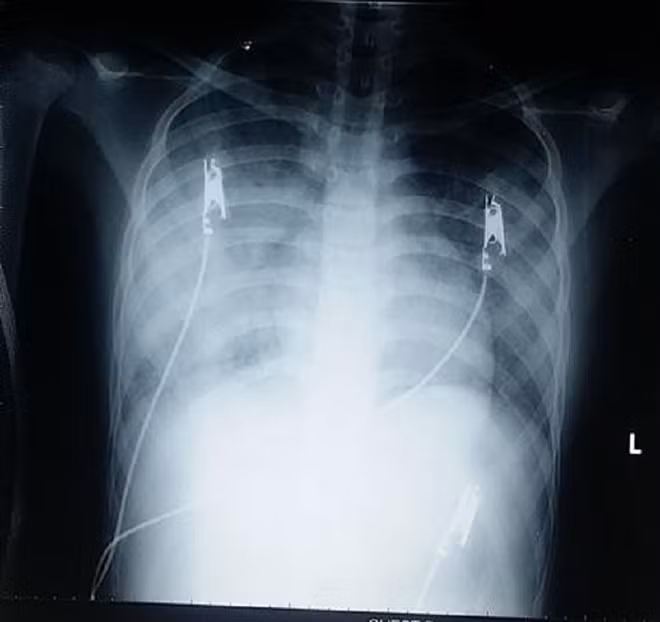

Ảnh chụp X-quang phổi bệnh nhi.

Khi được đưa đến BV Nhi Đồng 2, các xét nghiệm ban đầu cho thấy tình trạng viêm phổi nặng, chụp x-quang ngực thâm nhiễm lan tỏa 2 phế trường nhưng các xét nghiệm nhiễm trùng không tăng nhiều.

Tổn thương trên kèm triệu chứng lâm sàng và tiền căn khiến các bác sĩ nghĩ đến hội chứng xuất huyết phế nang lan tỏa nên đã cho bệnh nhân chụp CT và tiến hành nội soi phế quản bằng ống soi mềm.